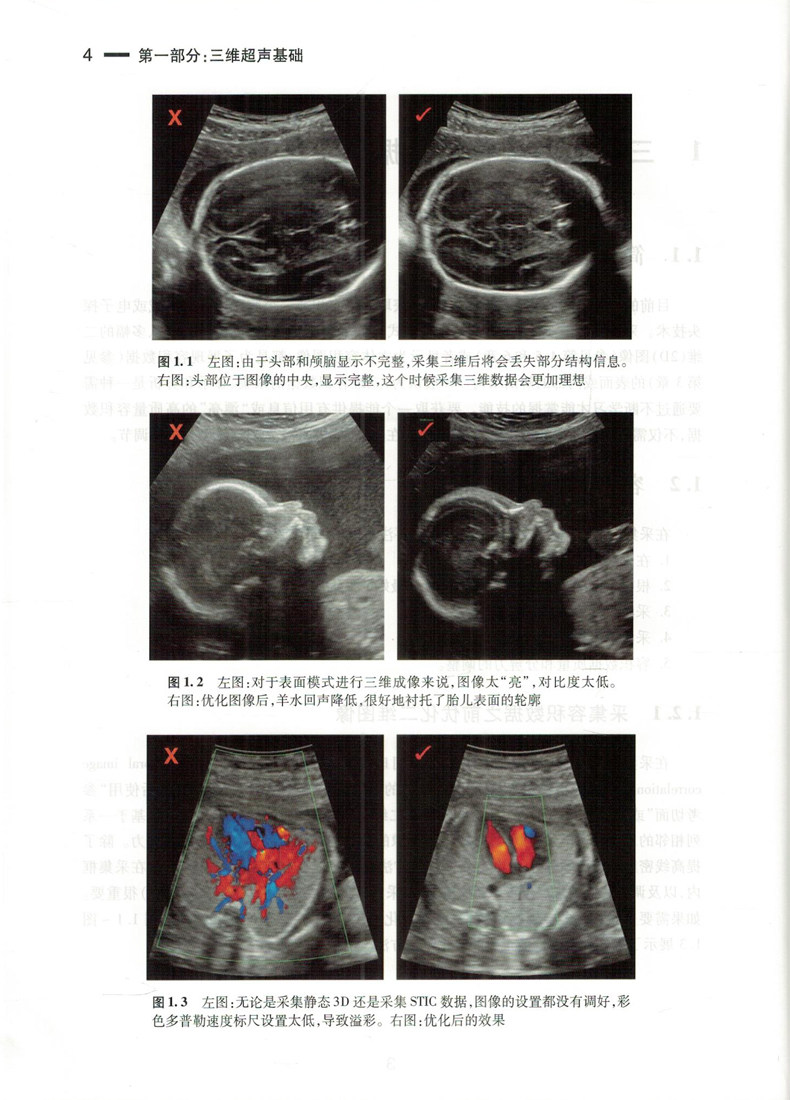

Подлинное пятно Трехмерное ультразвук при пренатальной диагностике, применяемое Схи Хоннинг, главный перевод акушерства и гинекологических схем Трехмерные ультразвуковые диагностические диагностики, укрепленные книгами, книги «Люди» 9787117263627